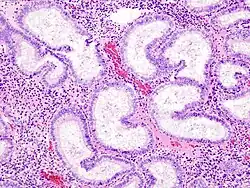

Hämatoxylin-Eosin-Färbung

Die Hämatoxylin-Eosin-Färbung, oft abgekürzt als HE-Färbung, ist ein Färbeverfahren in der Histologie, mit dem die verschiedenen Strukturen eines feingeweblichen Schnittes angefärbt werden können.

Die Hämatoxylin-Eosin-Färbung dient der Unterscheidung verschiedener Gewebestrukturen im mikroskopischen Bild anhand von zwei verschiedenen Einzelfärbungen und ist eine der am weitesten verbreiteten Routinefärbemethoden für morphologische Untersuchungen. In der Pathologie können mit Hilfe dieser Übersichtsfärbung krankhafte Veränderungen in Biopsien und Operationspräparaten untersucht werden. Die Methode dauert je nach verwendeten Protokollen und Färbelösungen zwischen fünf und 45 Minuten und ist oftmals Teil einer umfangreichen Gewebeverarbeitung, die ein bis mehrere Tage umfasst. Auch in der Forschung findet die HE-Färbung vielfältige Anwendung, insbesondere als Übersichtsfärbung vor der Anfertigung von immunhistochemischen Färbungen zur Untersuchung verschiedener Aspekte, wie z. B. bei der Diagnostik von Tumoren.[1] Tumoren mit einem Durchmesser von unter 0,2 mm können teilweise übersehen werden, weshalb die Hämatoxylin-Eosin-Färbung oftmals parallel zur Immunfärbung verwendet wird.[2]